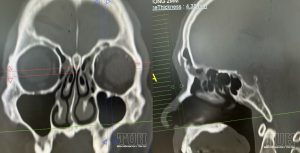

Chấn thương gây vỡ sụp khối mũi trán là loại chấn thương phối hợp đáng [...]